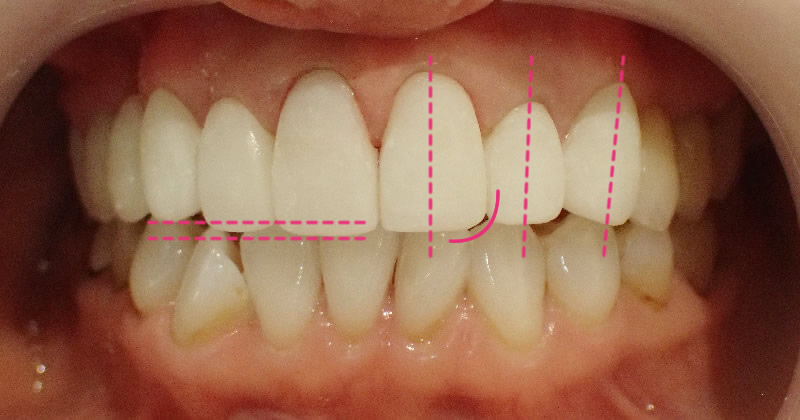

为前牙安装全瓷冠以矫正牙齿拥挤

治疗前

治疗后

这位患者的虎牙相比其他牙齿位置更高,整体牙列不整齐。通过全瓷冠矫正有效改善了以上情况。

安装全瓷冠后,上方的前牙排列变得更加和谐,使得口部在微笑或者说话时显得格外动人。